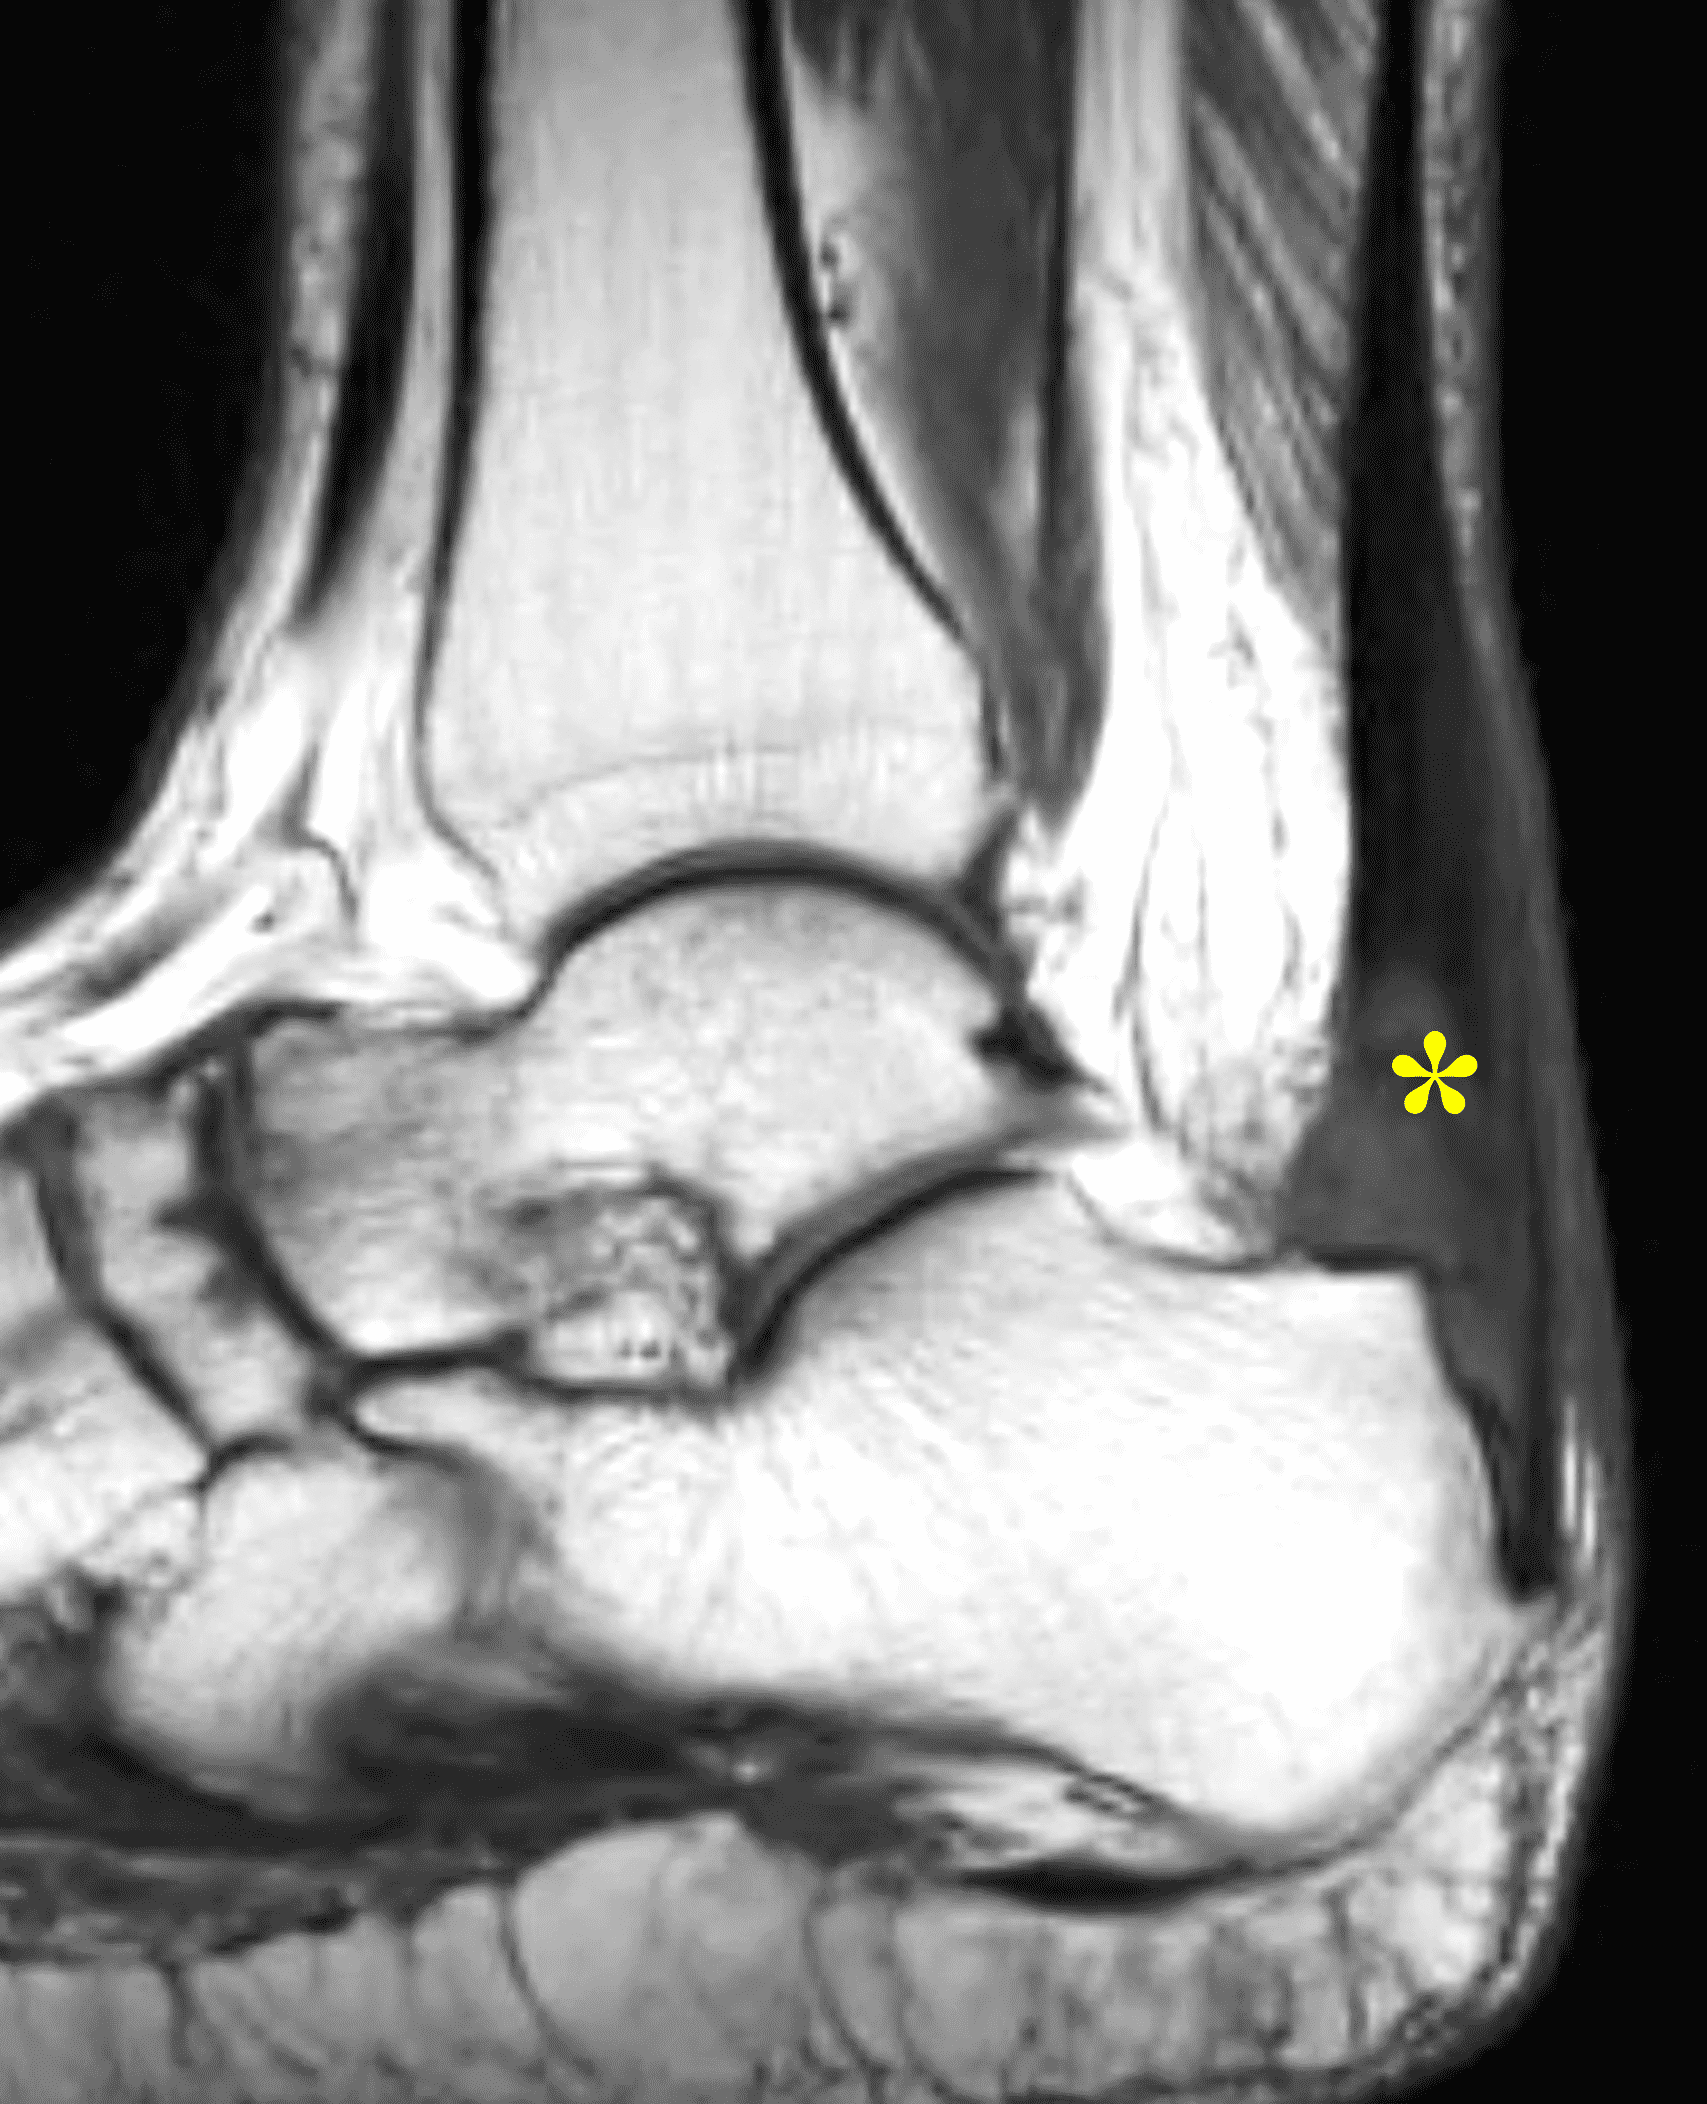

A 22 year-old male college football player presents with a “pop” and pain posterior to the right ankle during practice 1 week prior. He is unable to bear weight. Lateral radiograph (1A), sagittal fat-suppressed T2-weighted (1B), sagittal T1-weighted (1C), and transverse fat-suppressed T2-weighted images are provided. What is your diagnosis? What MRI findings affect clinical management decisions?

Figure 2: Complete Achilles tendon rupture. (2A) The lateral radiograph shows a thick and indistinct proximal Achilles tendon contour (arrows). (2B) A fat-suppressed T2-weighted image shows complete rupture of the tendon with a fluid-filled gap (yellow arrow) measuring 1.5 cm in length, located 10 cm cranial to the tendon insertion (blue arrow) and just distal to the edematous myotendinous junction (red arrow). The tear is superimposed on diffuse tendinosis. (2C) A sagittal T1-weighted image confirms the diffuse tendinosis. Fluid extends anteriorly into Kager’s fat pad (arrow) suggesting disruption of the anterior paratenon. (2D) A transverse fat-suppressed T2-weighted image through the proximal tendon shows no intact fibers (arrow), confirming the full-thickness rupture.

Acute, complete Achilles tendon rupture just distal to the myotendinous junction, superimposed on diffuse tendinosis.